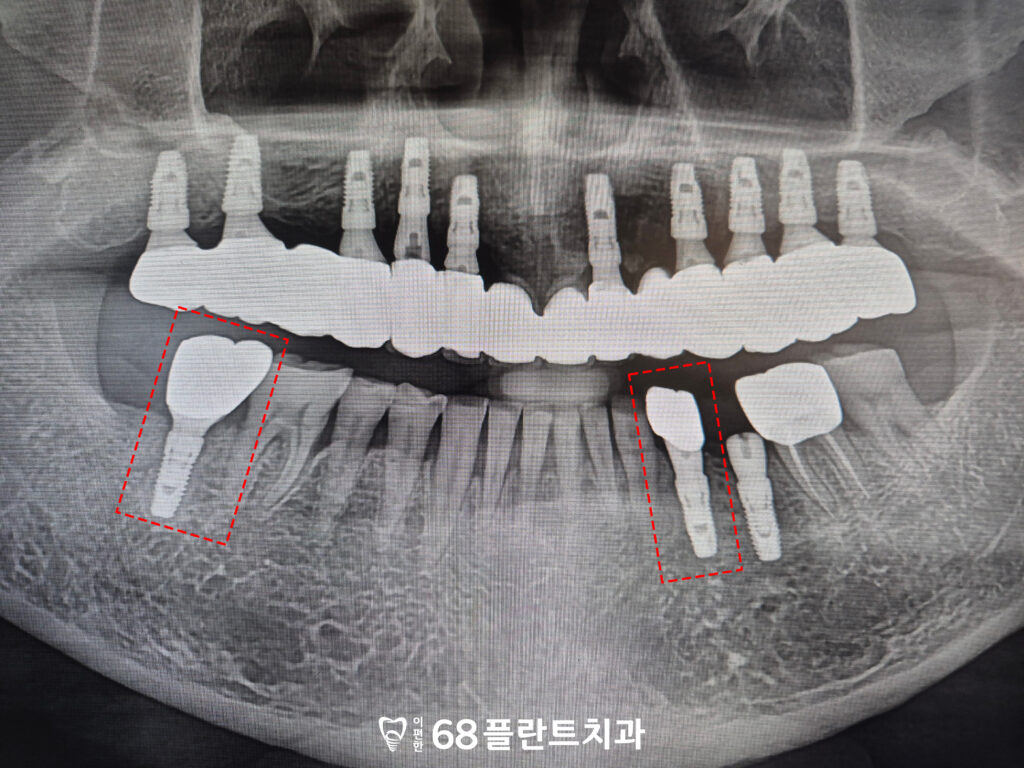

확인해 보니,

위쪽 어금니 양쪽이 전부

치아가 상실된 상태였으며

남아있는 앞니는

치주염으로 인해 잇몸뼈가 소실되어 있었습니다.

이로 인해, 치조골 지지가 충분하지 않아

저작 시 힘을 버티기 어려운 상황이었고

이미 염증이 반복되면서

예후 또한 좋지 않은 상태로 판단되었는데요.

그래서 본원에서는

위 치아 전부 발치 후

철산역임플란트를 통해

기능을 회복하기로 계획을 수립하였습니다.

또한 오른쪽 아래 맨 뒤 치아는

맞닿는 위 치아가 없어

점점 정출되어 올라온 상태였습니다.

대합치가 없는 상태가 오래 지속되면서

해당 치아가 위로 자라 나오듯 이동하였고,

그로 인해 교합 평면이 흐트러진

모습이 확인되었습니다.

그리고 해당 치아 역시

치주염의 영향으로

치근분지부까지 골 소실이

진행된 상태였습니다.

그래서 발치 후 철산역임플란트를

함께 식립하기로 계획을 수립하였습니다.

먼저 예후가 불량하다고 판단된

치아를 전체적으로 발치하고,

사전에 계획한 위치에 맞춰

임플란트를 식립하였습니다.

위쪽에 전체적으로

식립이 이루어졌기 때문에

교합의 균형과 식립 각도, 깊이를

더욱 정밀하게 고려해야 했습니다.